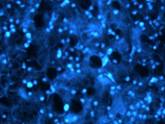

UV fluorescence image (Nikon) of B16 melanoma without nanoparticles (x 60) |

UV fluorescence microscopic image (Nikon) of B16 melanoma after uptake of AuSPION . The image is shifted from green to blue due to the uptake of gold nanoparticles (x 60)

We have observed the fluorescent aspect of tumor cells surrounded by healthy tissue, due to penetration of nanoparticles by means of endocytosis. The tumor limits can be seen clearly. |